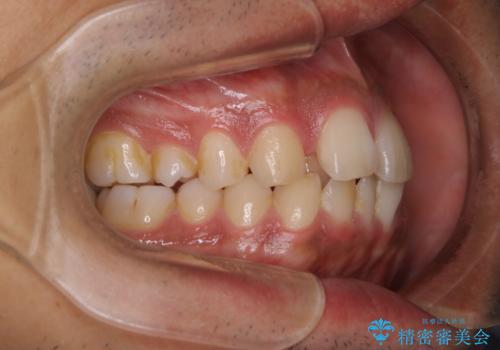

矯正をスタートする前にクリーニングを行いました。PMTC60分コースを行いました。

10年ぶりのクリーニングのため着色や歯石、プラークの量は多めでした。